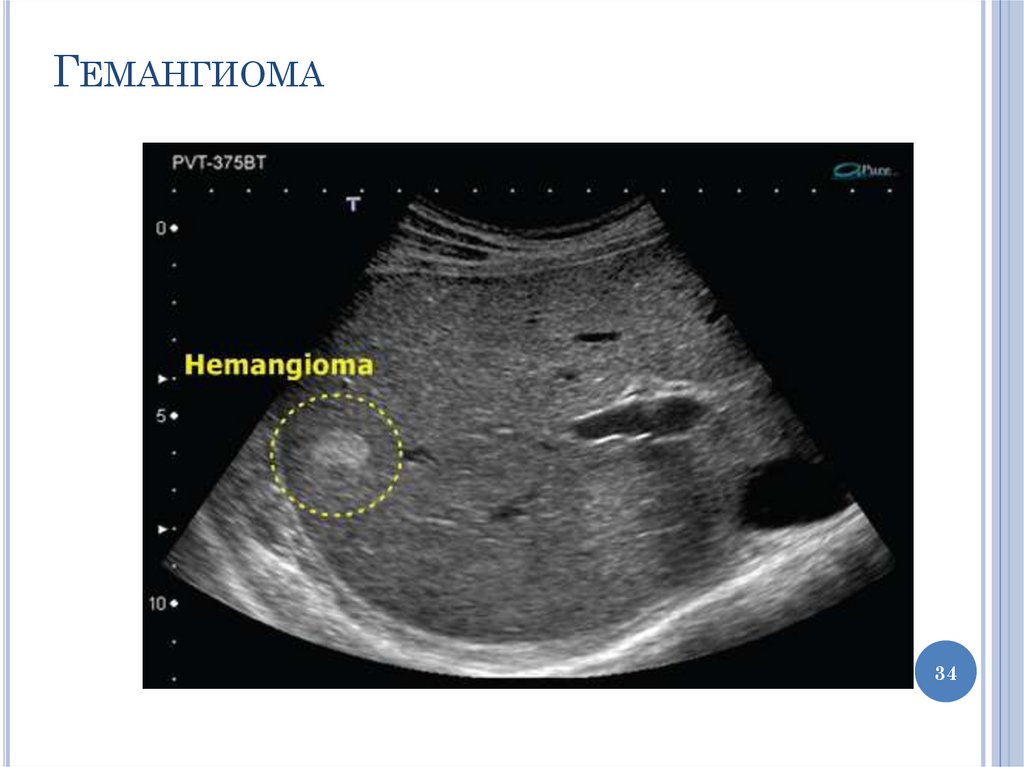

34.

ГЕМАНГИОМА

34